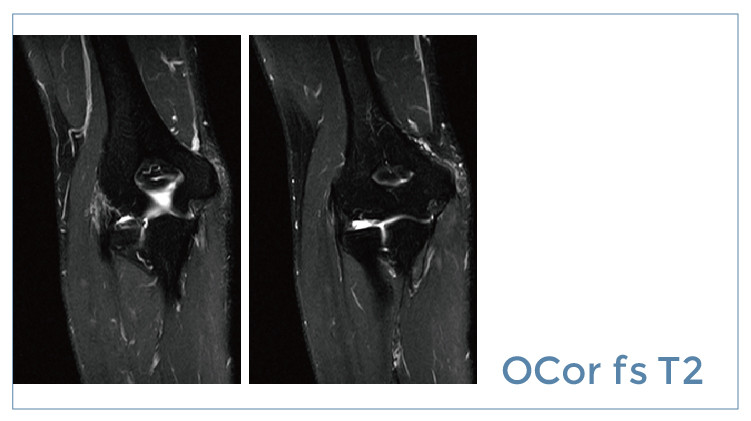

【朗润影像档案】磁共振影像病例分享(编号20190726)